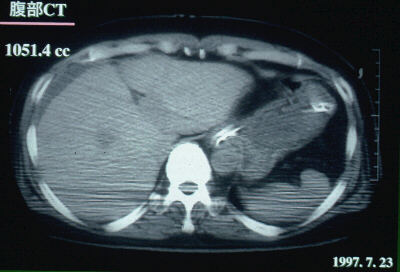

1997.7.23:腹部CTスキャン

肝容量は1051.4ccまで、回復。